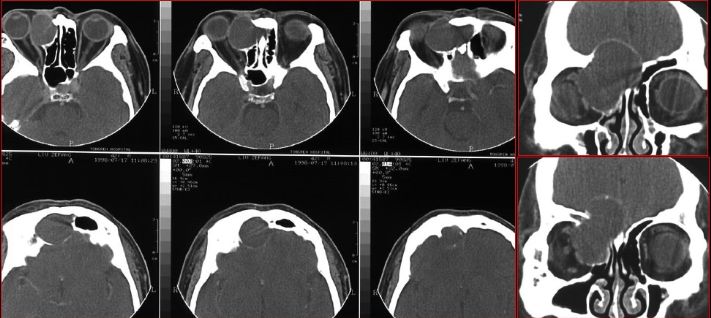

慢性多发鼻窦炎鼻息肉

慢性多发鼻窦炎—MRI